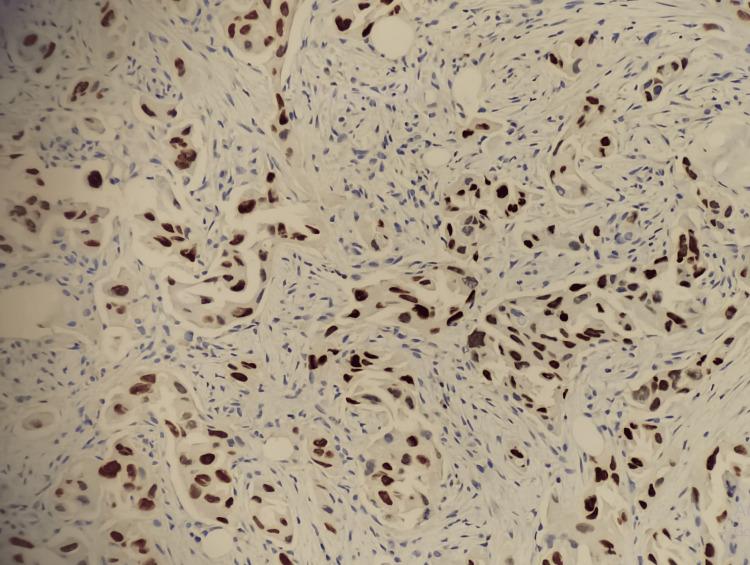

我们报告了沙特阿拉伯首例通过逆转录-聚合酶链反应技术证实存在 Kirsten 大鼠肉瘤病毒癌基因同源物(KRAS)G12C 突变的两例肺腺癌患者的病例系列。两名患者均为男性,年龄分别为 64 岁和 76 岁。第一名患者有重度吸烟史,而第二名患者未报告任何吸烟史。两例患者的肿瘤亚型均被确定为非黏液性肺腺癌。较年轻的患者表现为全身淋巴结肿大和右侧肺部肿块病变,而较年长的患者表现为 III - A 期左肺腺癌,需要快速治疗。对第一例病例的初步检查显示右侧纵隔移位、双侧颈部淋巴结肿大,以及右锁骨上核心活检的低分化肿瘤,导致采用姑息治疗并定期检查。第二例病例在确认生命体征稳定且实验室检查(中性粒细胞 100)后无发热症状。需要进一步开展研究,特别是针对大量来自阿拉伯湾地区的患者,以确认本国人群与国际人群之间的显著差异。此外,未来的研究应调查阿拉伯湾地区患者与其他患者之间 KRAS 突变型肺腺癌分化方面的更多差异。